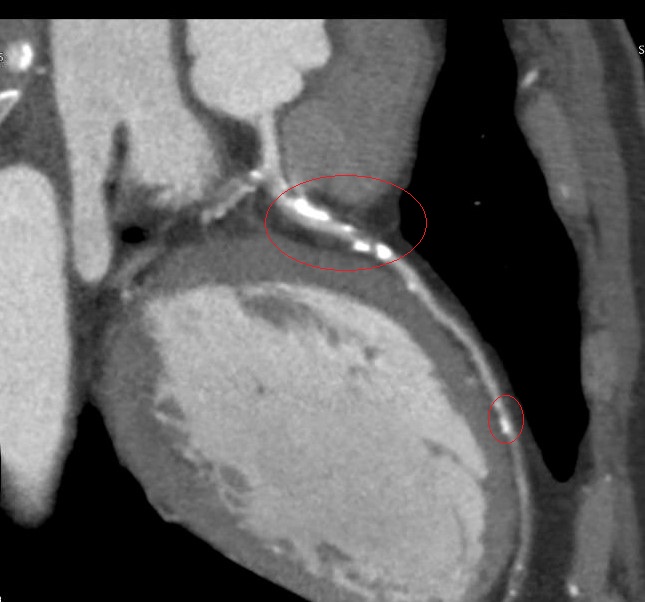

▲心臟冠狀動脈電腦斷層顯示林先生冠狀動脈鈣化阻塞。(圖╱彰化醫院提供)

▲李學林醫師指出,林先生進一步做心臟冠狀動脈電腦斷層,確認為3條主要冠狀動脈血管內鈣化狹窄達85%以上,若未及時處理,隨時可能引發急性心肌梗塞。(圖╱彰化醫院提供)

李學林表示,林先生日前接受肺癌篩檢時意外發現心血管鈣化,但無法確認是血管內或血管外鈣化。因患者平時已出現胸悶症狀,進一步做心臟冠狀動脈電腦斷層,確認為3條主要冠狀動脈血管內鈣化狹窄達85%以上,若未及時處理,隨時可能引發急性心肌梗塞。